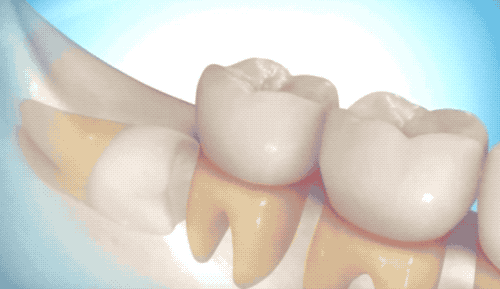

難度一英雄模式

用高速旋轉(zhuǎn)的渦輪機(jī),把牙齒磨成兩半,依次撬出來(lái)。